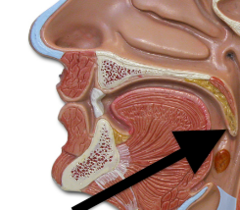

Hard/soft palate

Inferior/middle/superior concha (s.) conchae (pl.)

Nasal Cavity

Nasal septum

Naso/oro/laryngo-phraynx

Oral Cavity

Paranasal sinuses

Tongue

Uvula

Vestibule (of nasal cavity)

Vocal folds (=vocal cords)

Epiglottis

Larynx

Trachae

Esophagus